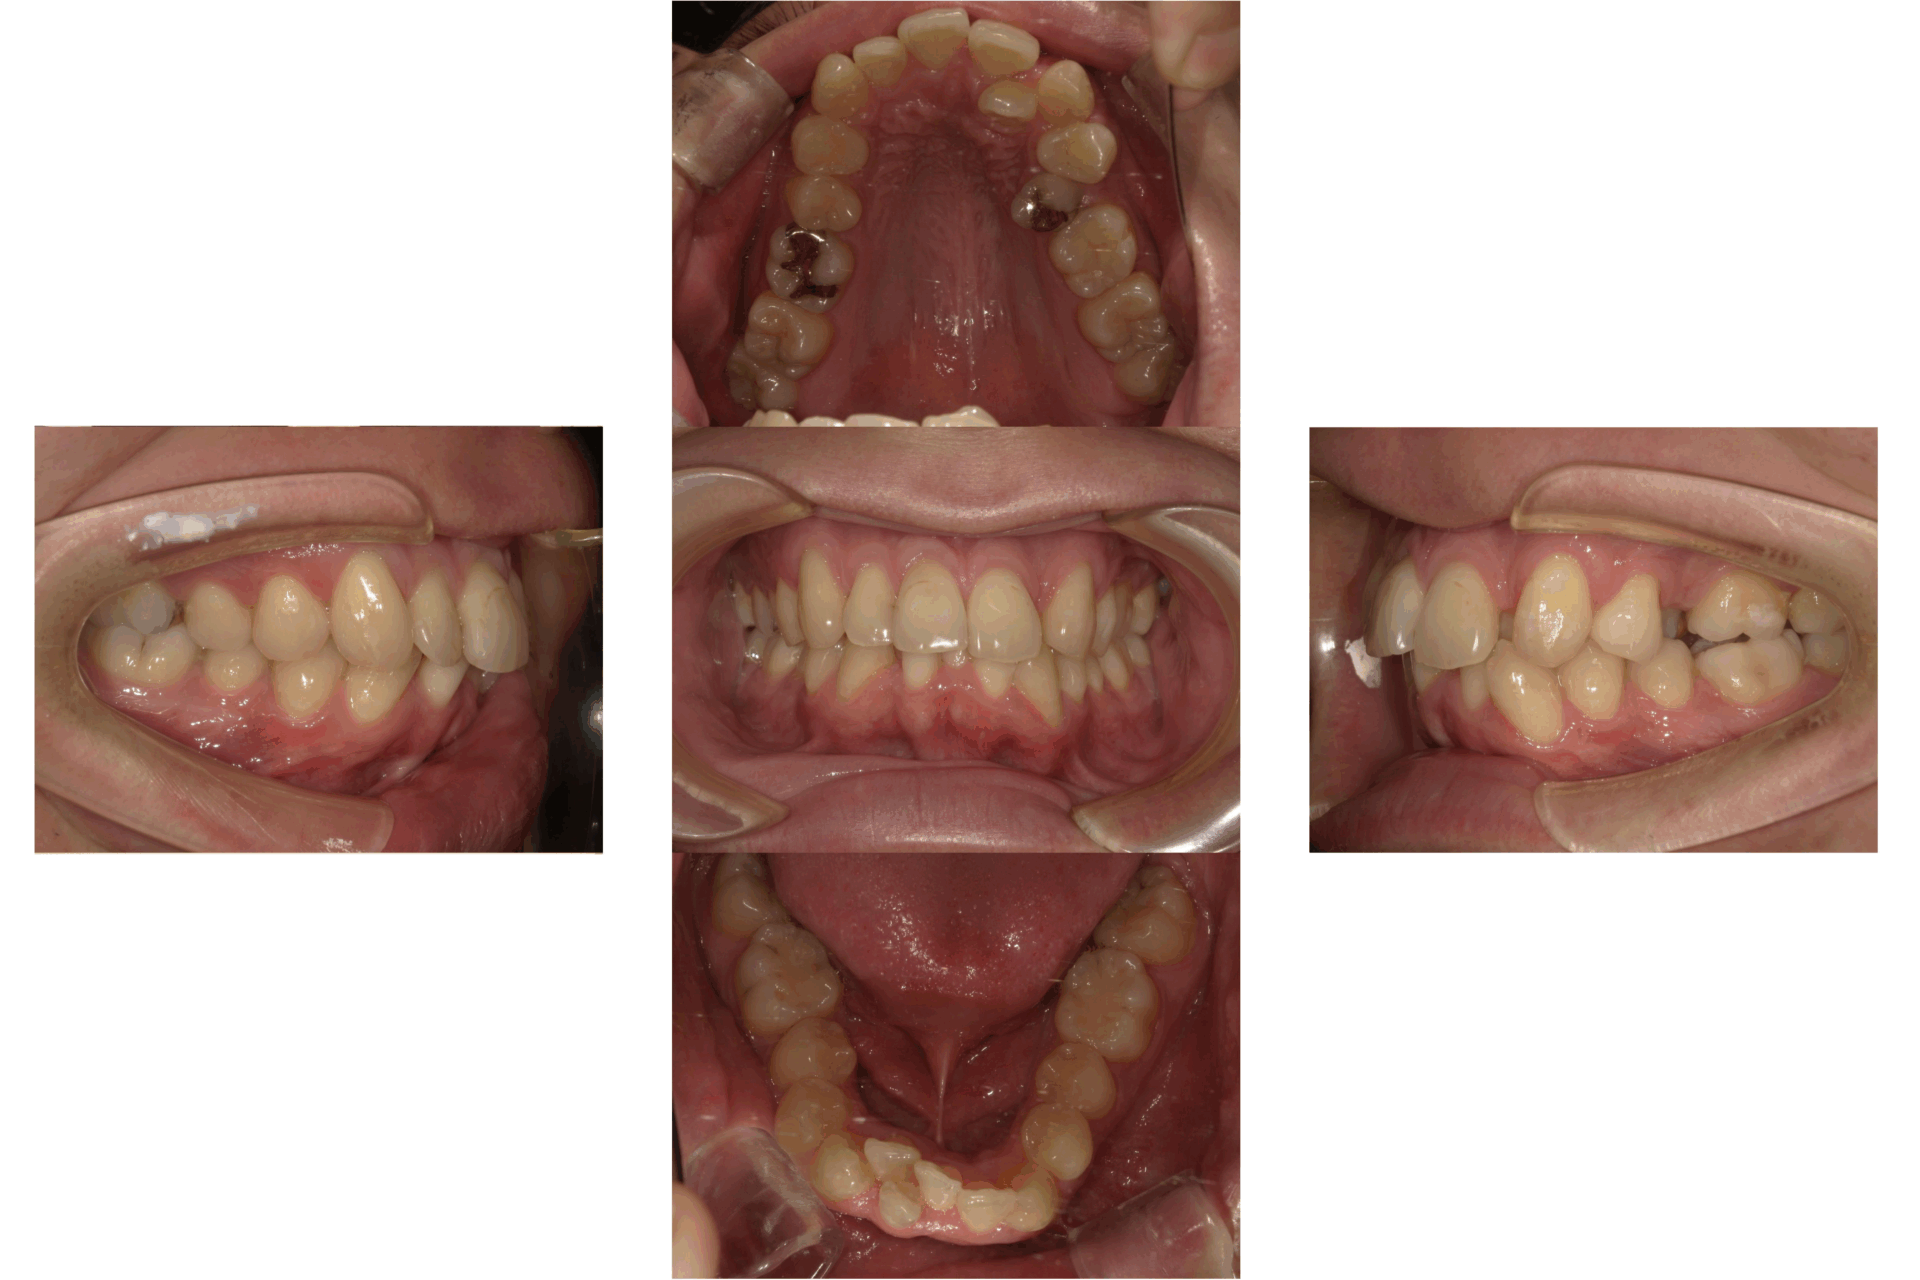

20代、女性、ワイヤー

| 施術内容 | 主訴:口ゴボが気になる。 詳細:ワイヤー矯正での歯並び改善 口元がかなり変化し、とても満足された症例です。 |

| 治療期間 | 16ヶ月(3/24現在 治療終了) |

| 費用 | ワイヤー矯正 60万円(税込660,000円) |